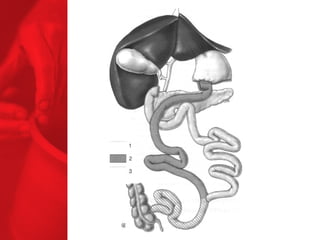

GASTRIC BYPASS Lesprocédures de malabsorption et restrictives > 56% de perte de poids excédentaire après quatre ans* > diminue le diabète de type 2 chez plus de 83 % des patients* *Christou NV, Sampalis JS, Liberman M, et al. Surgery Decreases Long-Term Mortality, Morbidity, and Health Care Use in Morbidly Obese Patients. Annals of Surgery 2004;240(3):416-424. ** Buchwald H, Avidor Y, Braunwald E, et al. Bariatric Surgery—A Systematic Review of the Literature and Meta-analysis. Journal of the American Medical Association 2004 Oct 13;292(14).

GASTRIC BYPASS Les procédures de malabsorption et restrictives >  56% de perte de poids excédentaire après quatre ans* > diminue le diabète de type 2 chez plus de 83 % des patients* *Christou NV, Sampalis JS, Liberman M, et al. Surgery Decreases Long-Term Mortality, Morbidity, and Health Care Use in Morbidly Obese Patients. Annals of Surgery 2004;240(3):416-424. ** Buchwald H, Avidor Y, Braunwald E, et al. Bariatric Surgery—A Systematic Review of the Literature and Meta-analysis. Journal of the American Medical Association 2004 Oct 13;292(14).